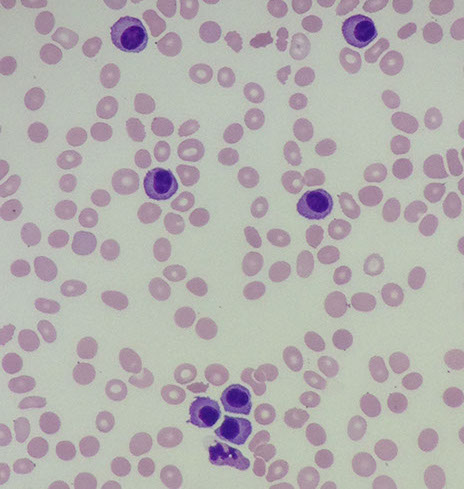

Indolent cancer of B-cells with "hairy" cytoplasmic projections, oval nuclei and lots of cytoplasm

PB: large lymph (double size of normal lymph) c round or reniform nuclei c smooth contours, ground glass chromatin c indistinct to absen nucleoli

can have circumferential hairy projections caused by frayed cytoplasmic edge

Cells look hairy b/c of overexpression of Rho family of small GTPases and Gas7 molecule up-regulation (a growth-arrest molecule)